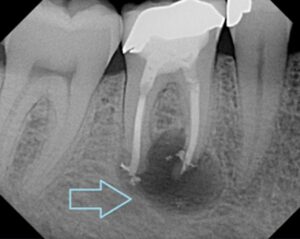

– Si kalon infeksioni nga goja në gjak Sëmundjet periodontale,si gingiviti dhe periodontiti ,shkaktohen nga baktere të cilat grumbullohen rreth mishrave dhe dhembëve .Kur mishrat janë të gjakosura dhe të inflamuara,këto baktere futen në qarkullimin e gjakut dhe nëpërmjet tij shkojnë në organet e tjera !

-Lidhjet me sëmundjet e zemrës: Bakteret orale dhe inflamacioni kronik ndikon në:

-ngushtimin e enëve të gjakut

-formimin e pllakave aterosklerotike

– rritjen e rrezikut për infark dhe sëmundjet koronare Ndikimi në tru dhe demenca. Studimet e fundit kanë treguar se bakteret orale mund të arrijnë në tru duke shkatuar inflamacion dhe dëmtime të indeve nervore .